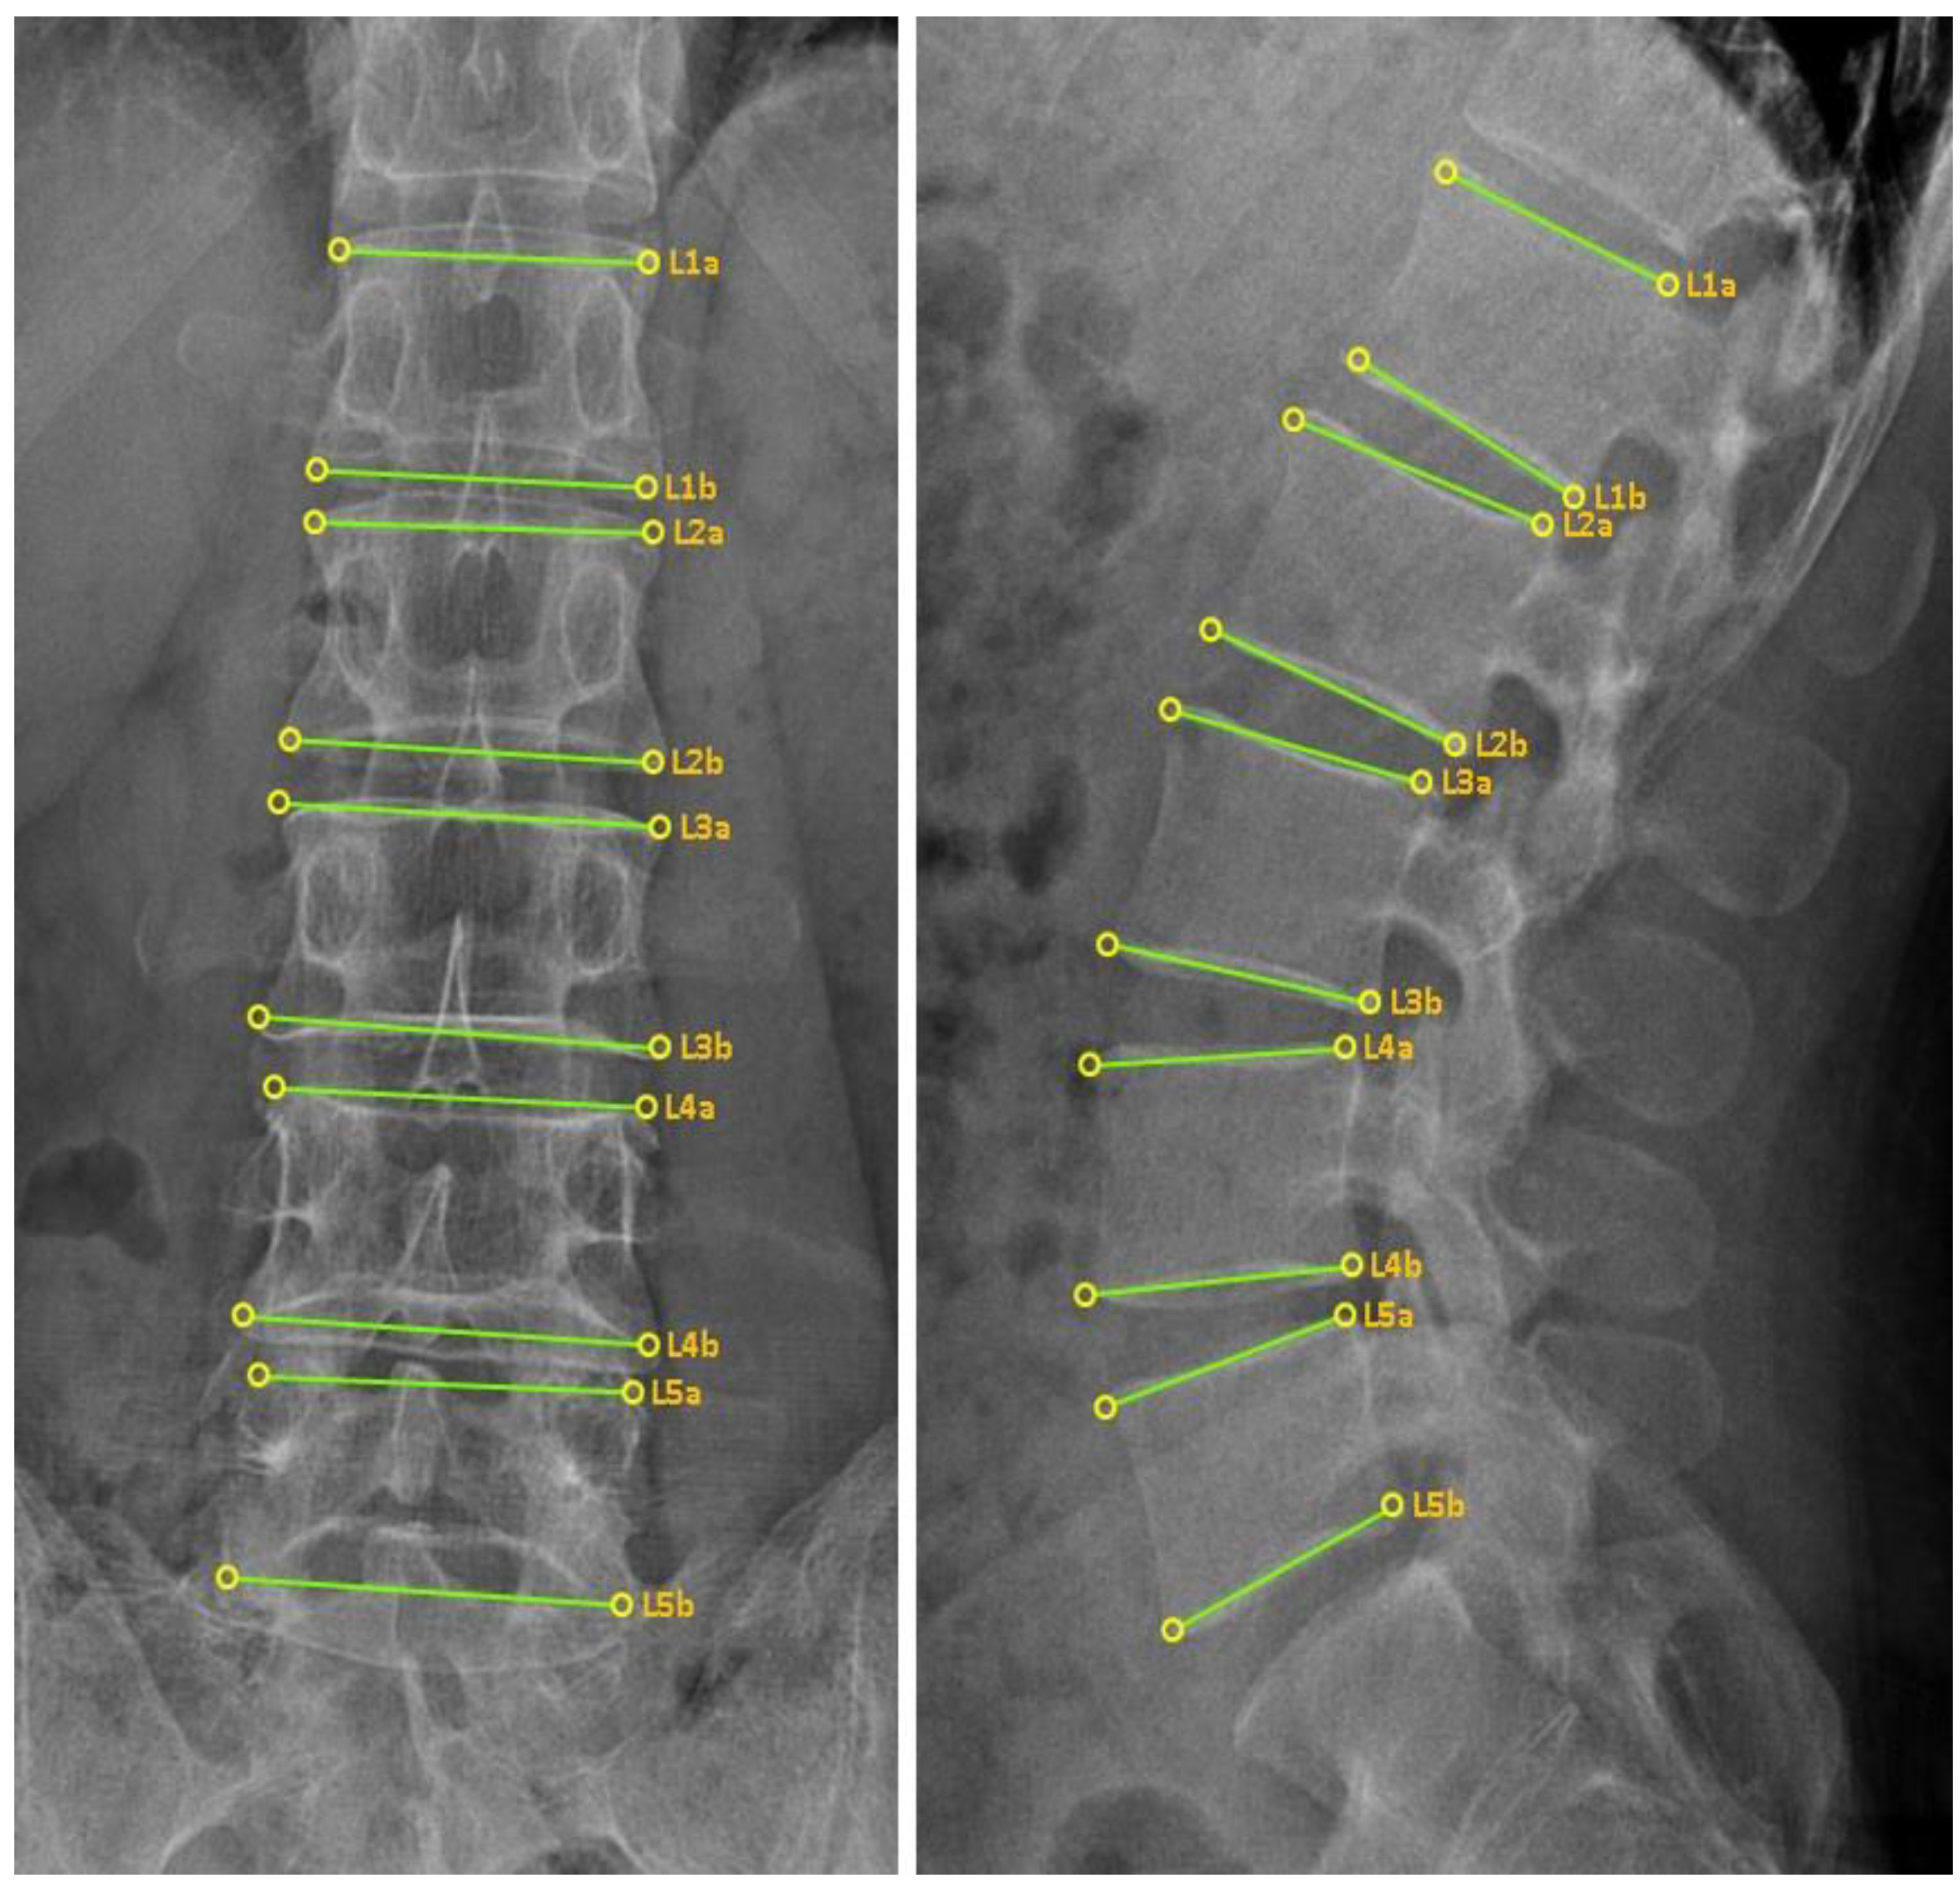

2.6.3. CMT X-ray Image-Based Diagnostic Method

2.6.4. CMT X-ray Image-Based Diagnostic Method Using the CMT-AI Program